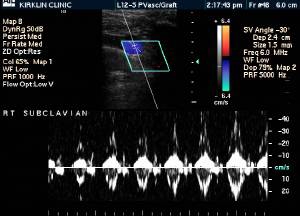

RADIOLOGY: VASCULAR: Case# 34603: NO EVIDENCE OF DEEP VENOUS THROMBOSIS. 53 year old male status post right total hip arthroplasty now with right leg swelling.